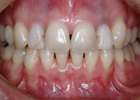

歯を抜いて治療した例 その1

治療後